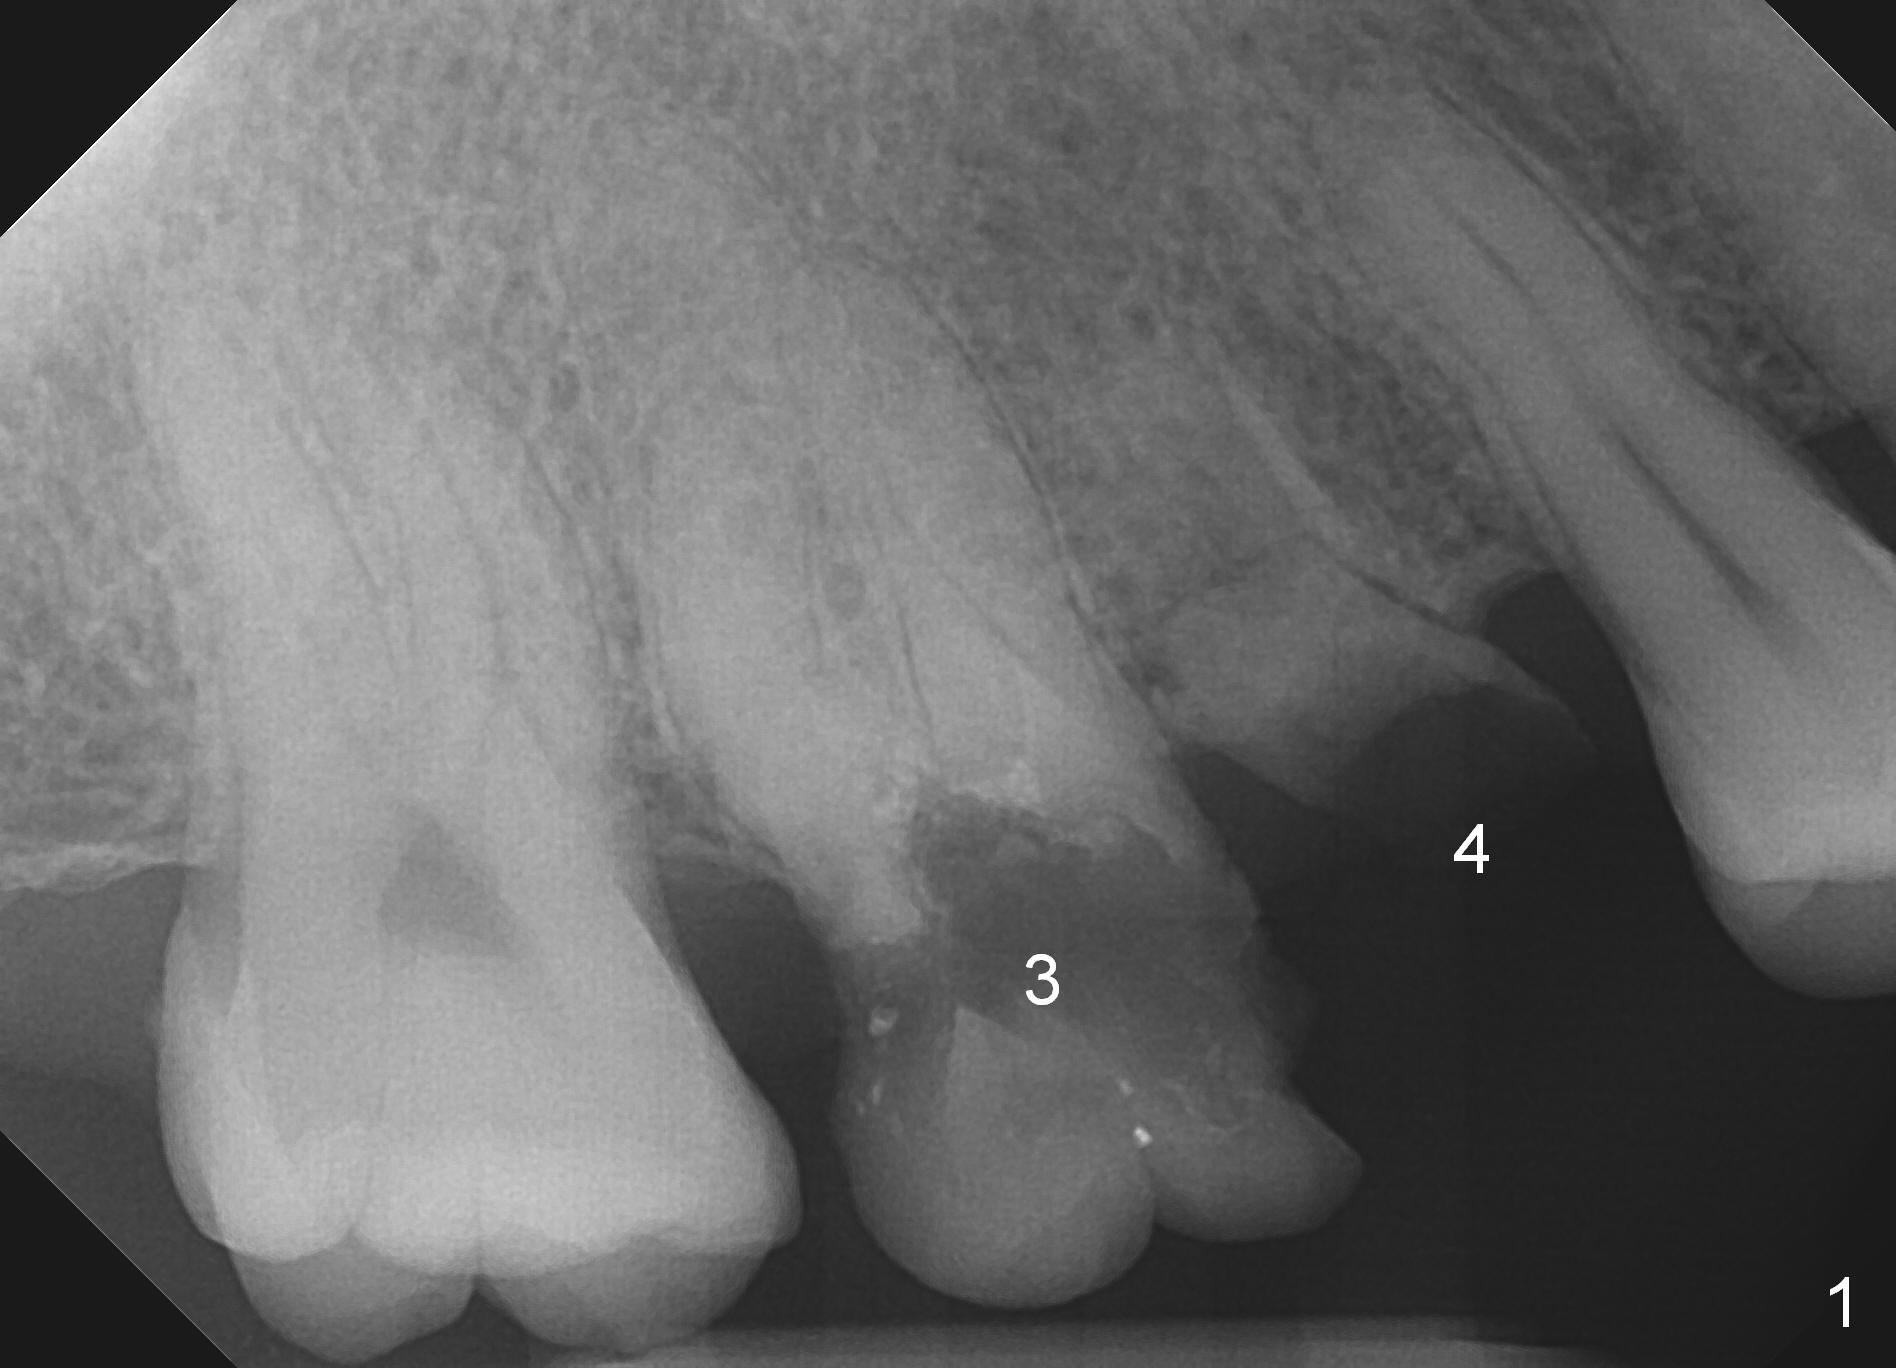

A 49-year-old woman (DC) requests treatment for residual roots at #3 and 4 after treatment of #9 (Fig.1). It appears that there will be no buccal or palatal wall defects. After extraction (no Antibiotic socket disinfection), osteotomy will be initiated with 1.6 mm pilot drill in the septum of #3, followed by Marking Bur (if the septum is pointed) and Magic Drill 3.3 mm for the full length (Fig.2), 3.8 mm for full length-2 mm. A 4.5 mm dummy implant is to be placed at #3 (underprep). If primary stability is low, place an implant of the next size. At #4 site, place a 4 mm dummy implant as palatal as possible (no prep). Measure the depth of the socket and the implant will be 1-2 mm shorter.